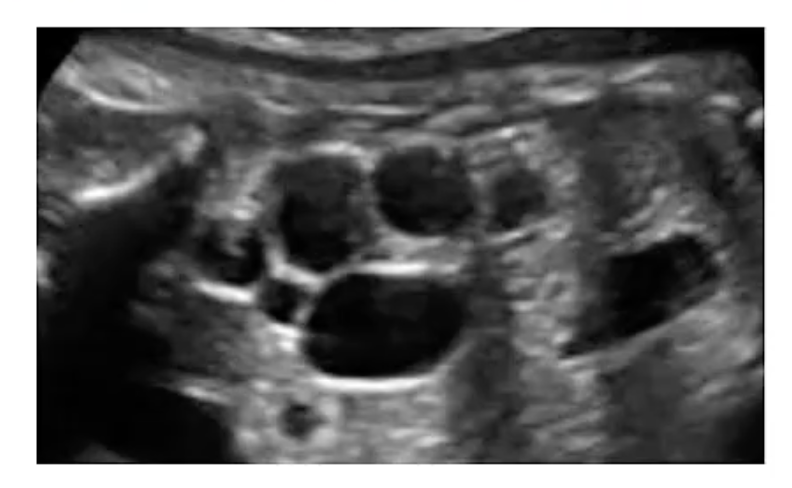

Autosomal dominant polycystic kidney disease

A

AD PKD typically manifests in pts age 40-50 e enlarged kidneys, flank pain and HTN; in newborns the kidneys are normal size and the cysts are too small to be detected; as the cysts enlarge, they compress renal parenchyma and cause symptoms